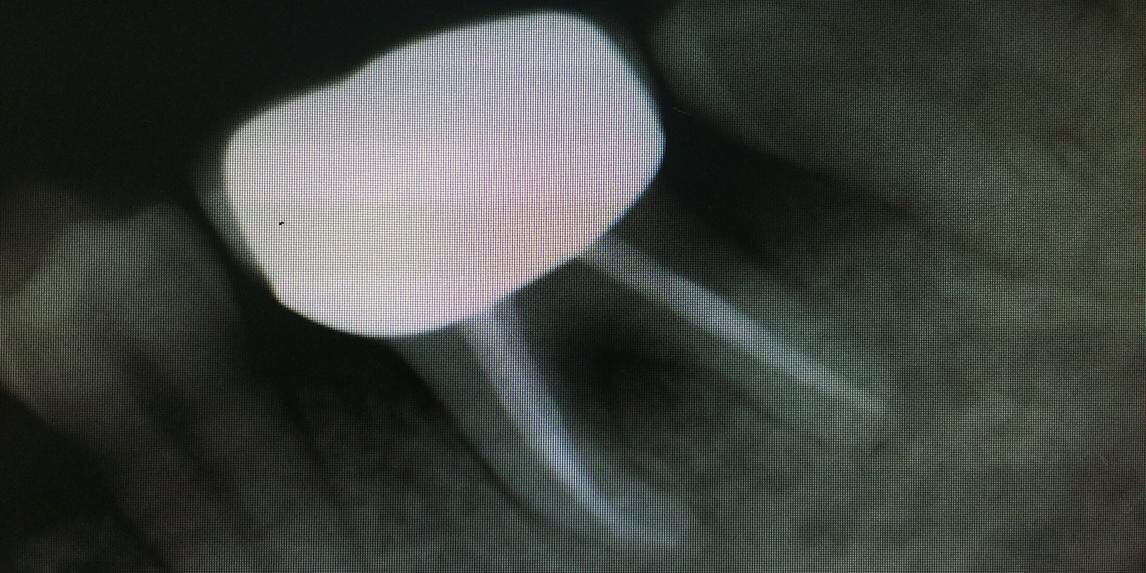

检查:36冠修复,叩诊(+-),松动II度,颊侧牙龈瘘管,牙周袋约3mm,根分叉未探及,冷(-)。 X线示:36根尖区及根分叉区大面积阴影。

20个月复查,36牙龈无红肿,牙体无松动。X线示36根尖及根分叉病变愈合。